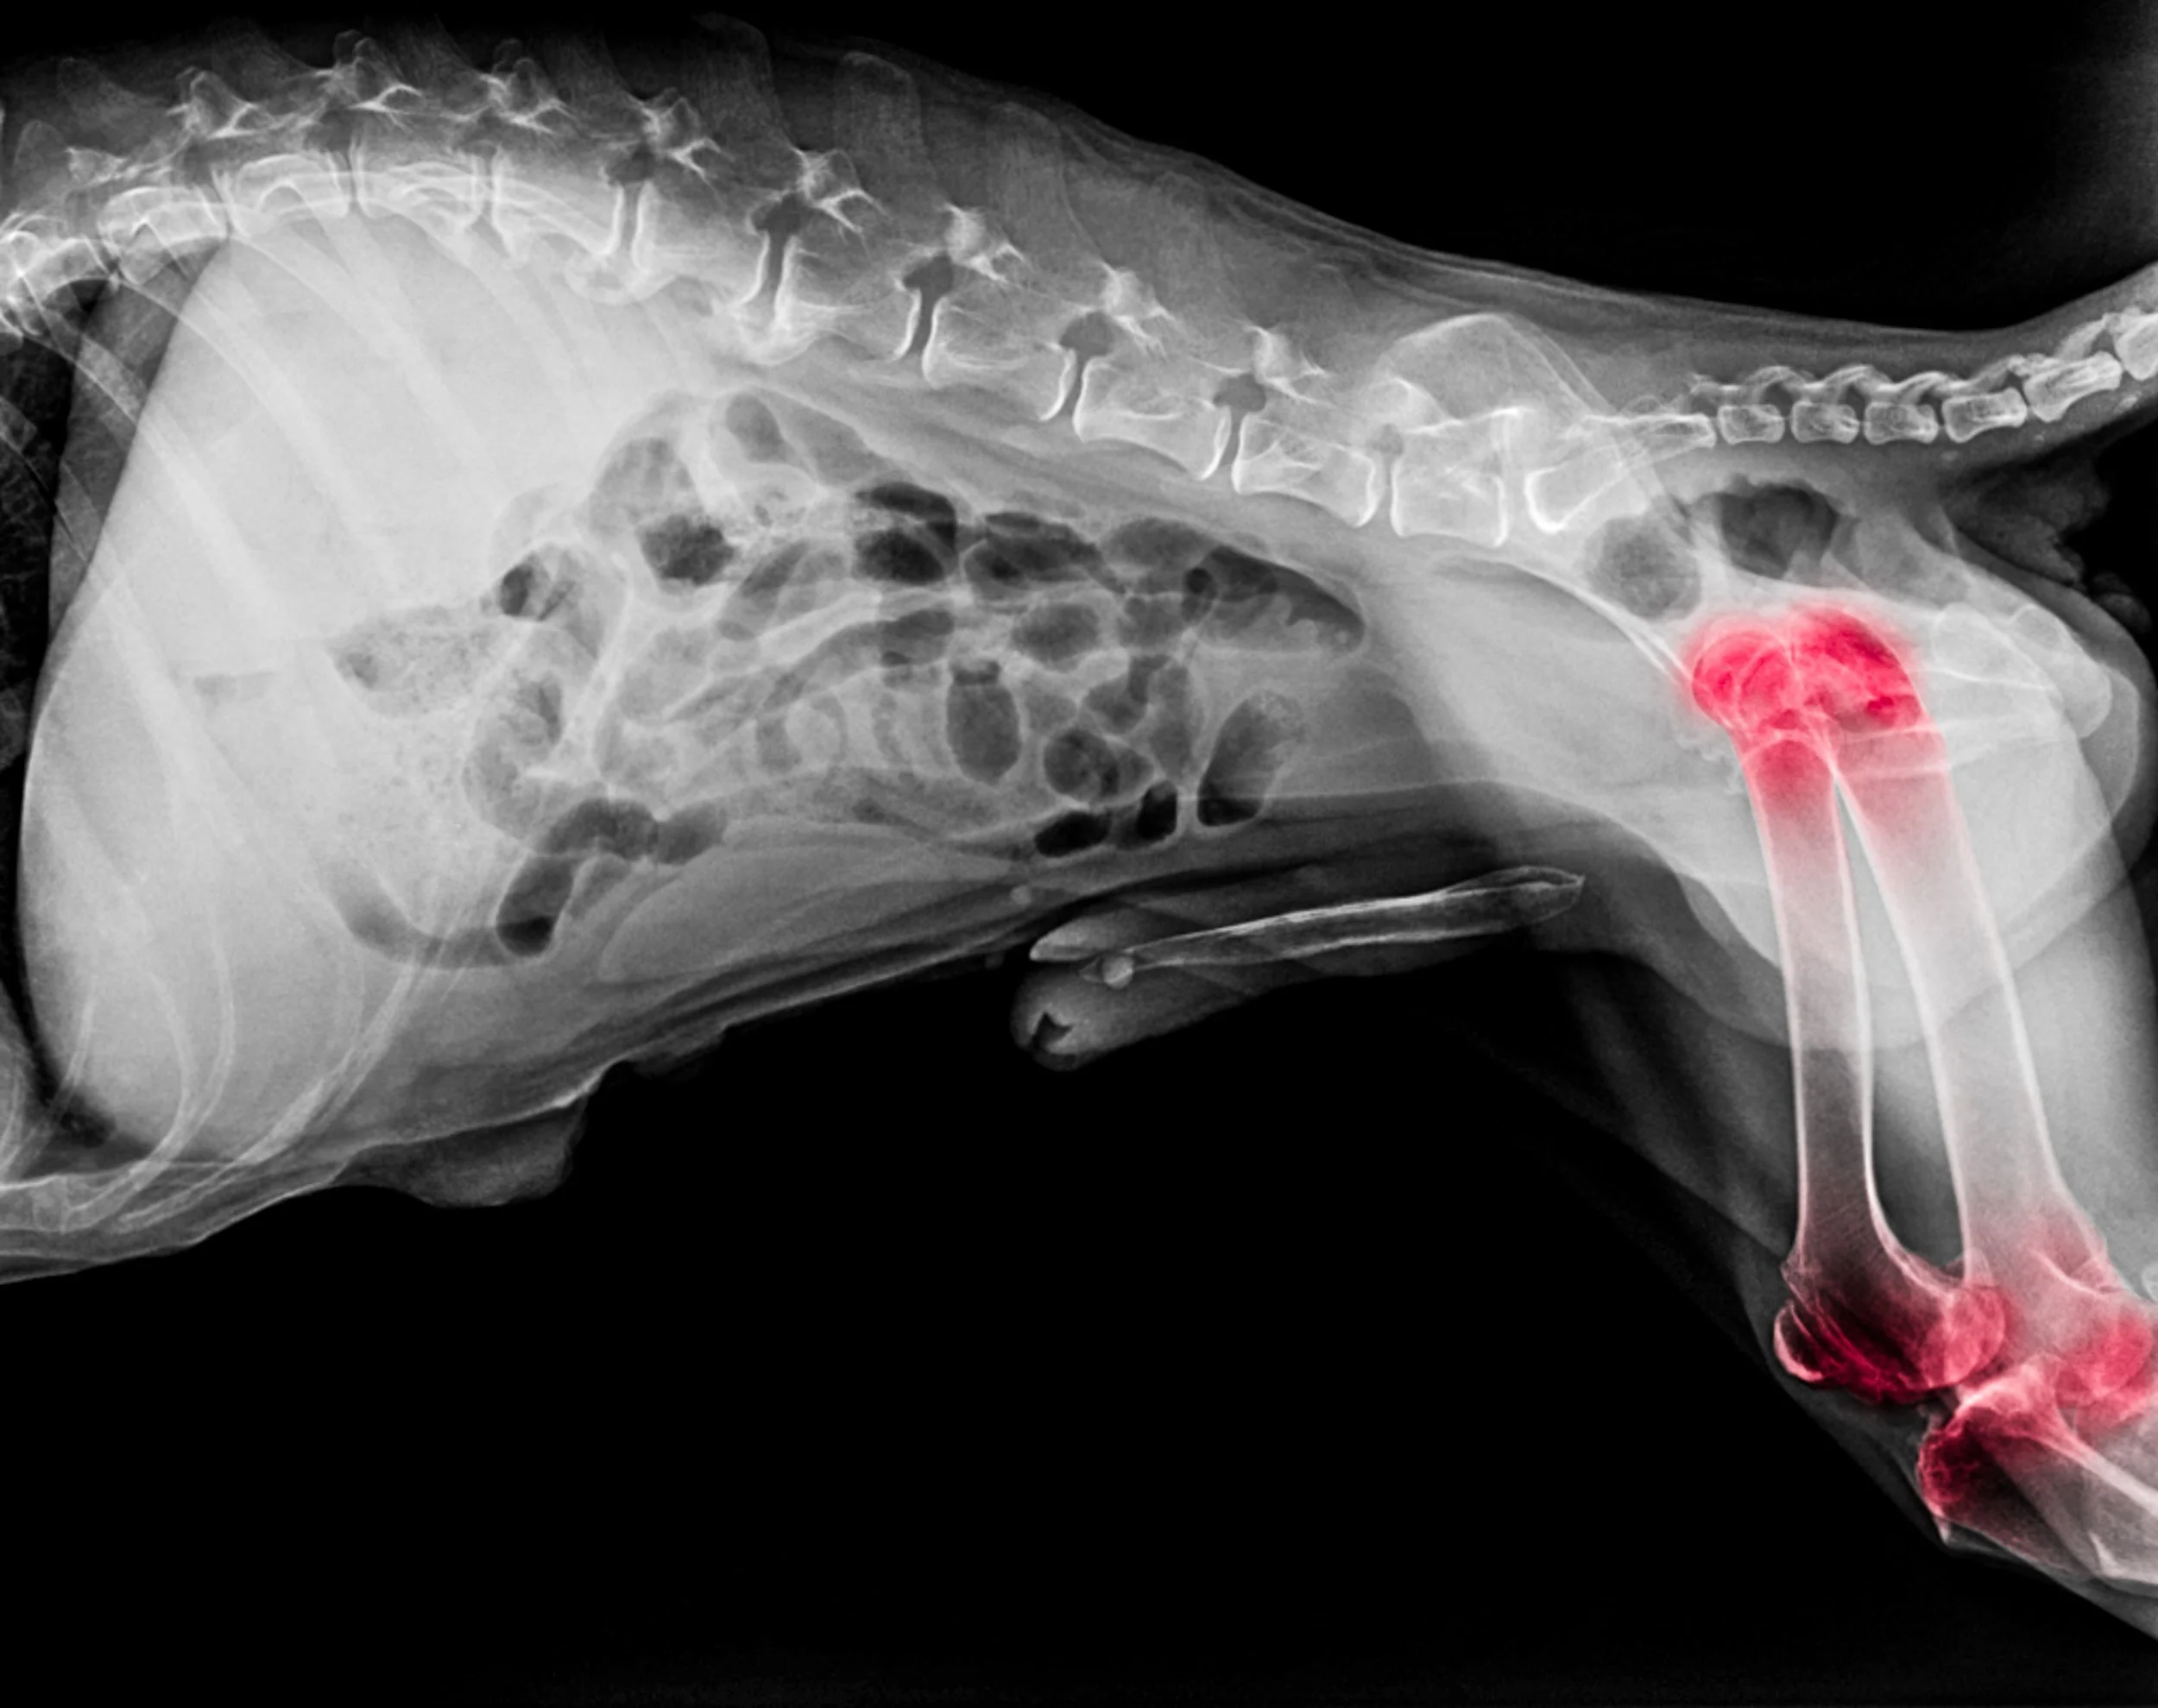

Radiograph of a dog highlighting joints commonly affected by osteoarthritis (hips and stifles)